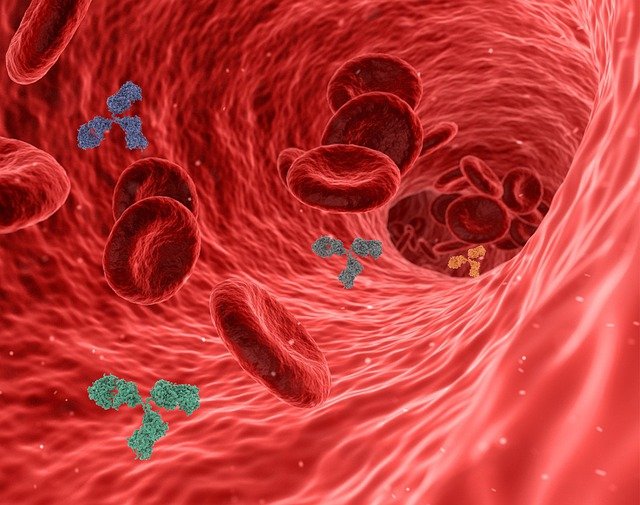

A team of researchers from the Rockefeller University, U.S. conducted a study that stresses on antibody evolution after vaccination against severe acute respiratory syndrome coronav...

A recent study has recently revealed that monoclonal antibody CT-P59 has antiviral potential against the delta variant of SARS-CoV-2. ...

A team of researchers from the University of California revealed that vaccines developed by Moderna and Pfizer-BioNTech against COVID-19 generate a coordinated adaptive immune respo...